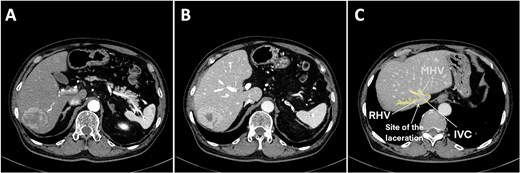

A 75-year-old man was referred to our institution for evaluation after the incidental finding of a liver tumor during routine surveillance. The medical history included a cerebral infarction 11 years ago, type 2 diabetes, hypertension, and percutaneous coronary intervention. He was taking aspirin daily, which was discontinued several days before surgery. The patient was asymptomatic at the time of presentation. The laboratory findings were normal and liver function was preserved (Child–Pugh A5). Dynamic contrast-enhanced computed tomography (CT) showed a solitary 53-mm lesion in segments 6 and 7, which was consistent with hepatocellular carcinoma (Fig. 1A and B). A laparoscopic posterior sectionectomy was planned.

Preoperative contrast abdominal computed tomography of a hepatocellular carcinoma tumor on the posterior segment. (A) Arterial phase, (B) venous phase, and (C) right and middle hepatic vein image with the laceration site marked. Abbreviations: IVC, inferior vena cava; RHV, right hepatic vein; MHV, middle hepatic vein.

Under general anesthesia in the left lateral position, three 12-mm and three 5-mm trocars were inserted into the abdomen. The right liver was mobilized by dividing the round, right coronary, and triangular ligaments, and the inferior right hepatic veins (IRHVs) and dissection around the right hepatic vein (RHV) and IVC. Parenchymal transection was performed with intermittent Pringle maneuvers. Massive bleeding suddenly occurred from the dorsal RHV near the RHV root (Figs 1C and 2A) during transection, likely extending to the anterior RHIVC (Fig. 2B). This bleeding may have been caused by excessive traction on the liver during transection. Laparoscopic hemostasis failed and the patient developed hemorrhagic shock with the systolic blood pressure dropping to 30 mmHg. Hakuzo Sterile OP Gauze NEO (2.5 × 10 cm and 4-ply; Osaka, Japan; Fig. 3D) was used to control bleeding.

Laceration of the IVC. (A) Right liver mobilization and hanging of the RHV by laparoscopy with the laceration site marked where the small, short hepatic vein was electrocauterized. (B) Hemorrhage from the IVC injury during laparoscopic surgery. (C ) The initial laceration on the IVC was ~1 cm in size and during gauze packing a small gauze migrated into the IVC through the laceration. (D) The IVC laceration extended to the root of the RHV. The laceration was ~5 cm in length and occupied one-half of the IVC circumference. (E) The laceration was closed with two sutures at the beginning and end of the laceration. (F) Hemorrhage was minimized with finger pressure. (G) The IVC laceration was repaired with continuous sutures using 4.0 Prolene sutures. (H) The IVC injury was successfully repaired. (I) Postoperative computed tomography image showing a reduction in the IVC diameter at the hepatic vein junction by approximately one-half. Abbreviations: IVC, inferior vena cava; RHV, right hepatic vein; IRHV, inferior right hepatic vein; S7, segment 7; S8, segment 8.

Emergency conversion to open surgery was performed. A 0.5-cm laceration (Fig. 2C) in the anterior RHIVC had extended to a nearly 5-cm tear involving the RHV root and nearly one-half of the IVC circumference (Fig. 2D). The extended laceration was likely caused by excessive compression applied during hemostasis with residual hepatic attachment to the IVC, under which even minimal traction exacerbated the tear. Hemorrhage was initially controlled by manual compression and two anchoring Prolene sutures at both ends of the laceration (Fig. 2E). Given the low central venous pressure (~5 cmH₂O), partial closure using two anchoring sutures and manual pressure (Fig. 2F) significantly reduced the bleeding. Hemostasis was achieved with continuous 4-0 sutures (Fig. 2G). The repaired RHIVC diameter was reduced by one-half (Fig. 2H and I). Hemodynamic stability was assured and the liver transection was completed. The total blood loss was 7729 ml, the intraoperative blood transfusion volume was 3640 ml, and the operative time was 535 minutes. The gauze count revealed one missing laparoscopic gauze. Despite thorough reinspection and intraoperative chest and abdominal X-rays, the gauze was not found. Given the patient’s unstable condition, the operation was concluded and the patient was transferred to the intensive care unit.